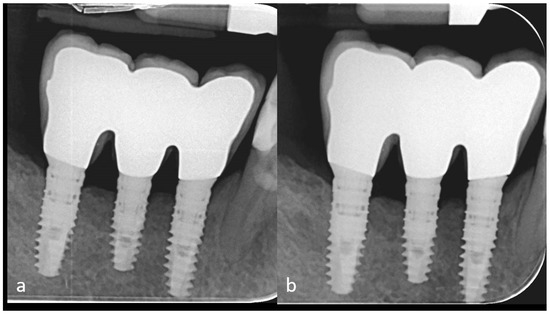

A Preshaped Titanium Mesh for Guided Bone Regeneration with an Equine-Derived Bone Graft in a Posterior Mandibular Bone Defect: A Case Report

2. Case Description